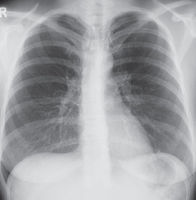

Konventionelles Röntgen

Die Röntgenuntersuchung steht für viele Fragestellungen auch heute noch an erster Stelle, weil sie einfach durchzuführen ist, eine relativ geringe Strahlenbelastung hat und einen schnellen Überblick über größere Körperabschnitte ermöglicht. Eine Röntgenröhre erzeugt Röntgenstrahlen, die die verschiedenen Gewebe des Menschen in unterschiedlichem Ausmaß durchdringen. Die Röntgenstrahlen treffen auf einen Detektor, der sie direkt in elektrische Impulse umwandelt („digitale“ Radiographie). Gegenüber den heute veralteten Röntgenfilmen hat ein digitales Röntgenbild den Vorteil, an vielen Bildschirmen gleichzeitig betrachtet, auf Massenspeichern archiviert und über Datenleitungen verschickt werden zu können.

Für die einzelnen Zentren der Kerckhoff-Klinik sind die wichtigsten Fragestellungen für die konventionelle Röntgenuntersuchung:

• Herzzentrum

Die wichtigsten Fragen der Kardiolog:innen und Herzchirurg:innen an den Radiologen betreffen Vergrößerungen der Herzkammern,  Einlagerung von Flüssigkeit um die Gefäße und Bronchien und die Entwicklung von Pleuraergüssen. Wichtige Begleiterkrankungen sind Entzündungen und Tumore. In der postoperativen Kontrolle nach Herzoperationen sind vor allem Komplikationen wie Entzündungen, Blutungen und Lufteintritt in das Rippenfell („Pneumothorax“) auszuschließen.

• Lungenzentrum

Eine zentrale Aufgabe in unserem Lungenzentrum ist die Diagnose und Behandlung von Lungentumoren. Hierfür stehen die Lungenaufnahme sowie die CT  im Vordergrund. Zum Nachweis oder Ausschluss von regionalen Lymphknoten- oder Organmetastasen bei malignen Lungentumoren gibt es in Bad Nauheim seit nunmehr acht Jahren ein PET-CT. Bei diffusen Lungenerkrankungen wie Lungenemphysem und verschiedenen Formen der Lungenfibrose liefert die Lungenaufnahme ebenfalls orientierende Informationen. In Deutschland führend ist das Lungenzentrum in der Diagnose und Therapie der  chronisch thrombembolischen pulmonalen Hypertonie (CTEPH), für die spezielle Erfahrungen auch in der Diagnostik mit Röntgen, CT und  MRT bestehen.